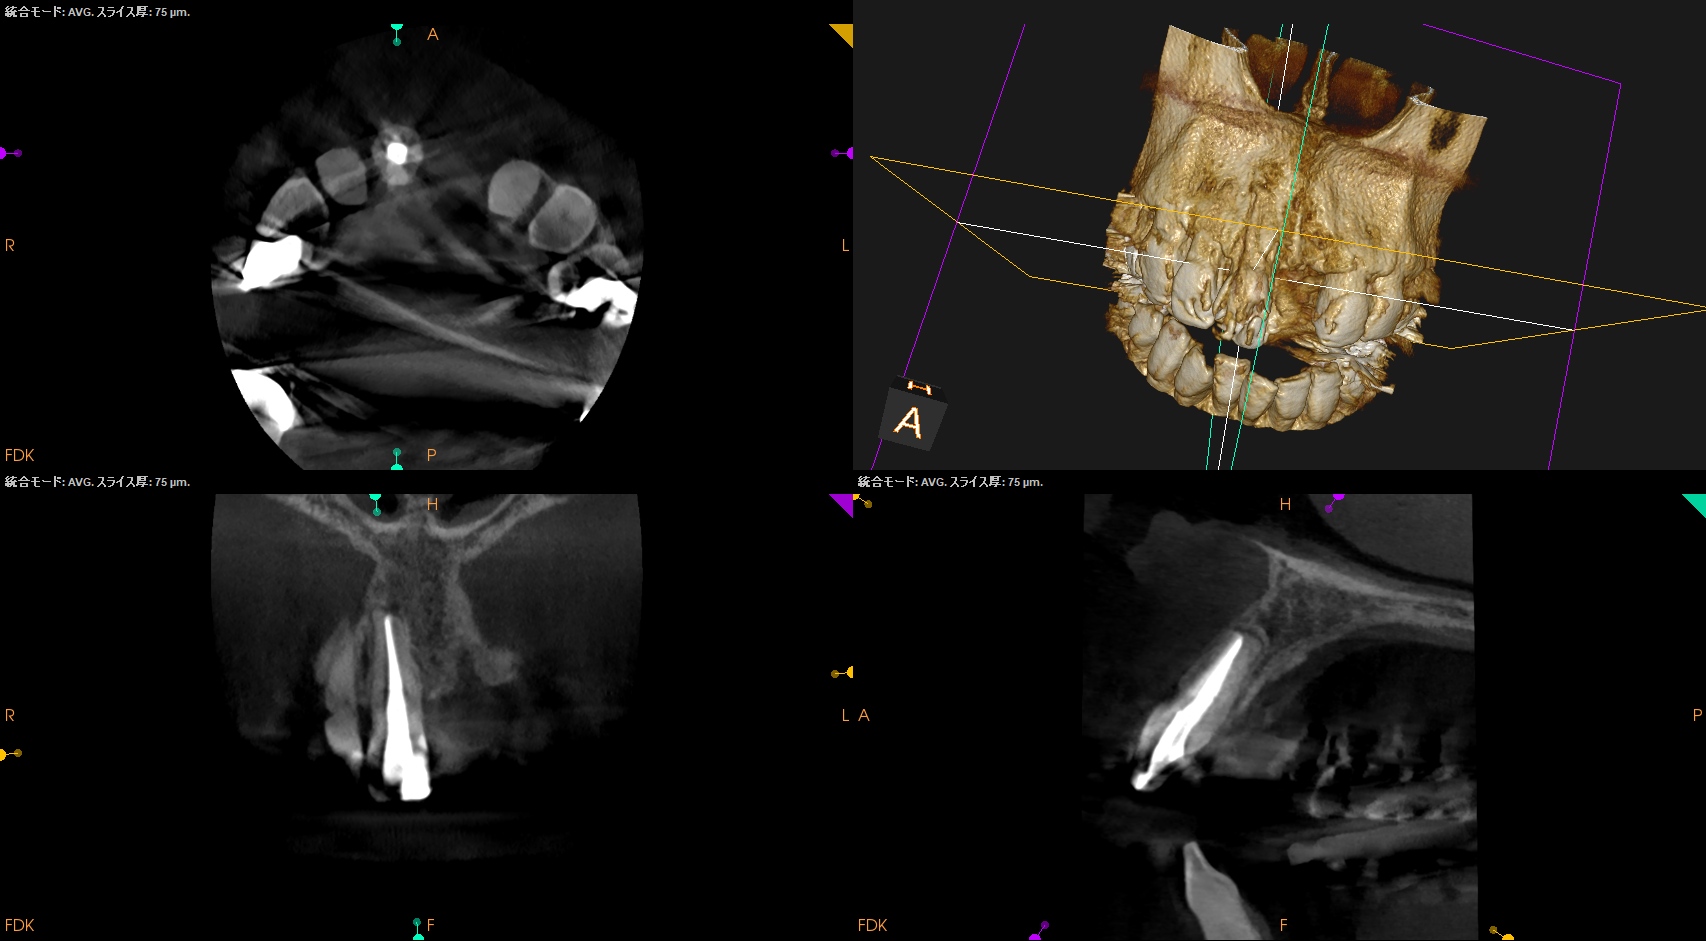

CBCT(2025.10.22)

この部分を攻略できれば勝機がある可能性が90%あるだろう。

攻略できなければ60%だ。

歯内療法学的診断(2025.10.22)

Pulp Dx: Previously treated

Periapical Dx: Symptomatic apical periodontitis

Recommended Tx: Re-RCT+Core build up with Fiber Post